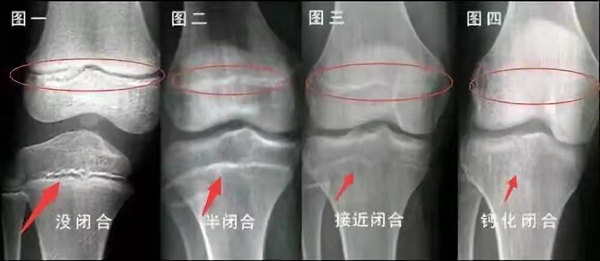

未成年時隨著年齡的增加骺軟骨端不斷骨化,骨骼就不斷增長。當(dāng)骨骺線完全閉合時骨骼就停止生長,個子也就不再增長了。一般骨骺端完全閉合的年齡是18~20歲左右。

青少年一般什么時候骨骺閉合?

一般女孩是在16歲,男孩是在18歲。

一般來說,女孩的骨齡超過14歲,男孩的骨齡超過16歲,這時其骨骺線已接近閉合,基本沒有長高的機(jī)會了。

因此,越早了解骨骺線閉合情況,越早干預(yù),孩子長高的可能性越大。